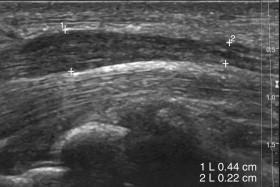

F igure 11-26, Carpal tunnel syndrome. Longitudinal view of the median nerve at the wrist level shows swelling of the nerve (0.44 mm vs. 0.22 mm) just proximal to the carpal tunnel.